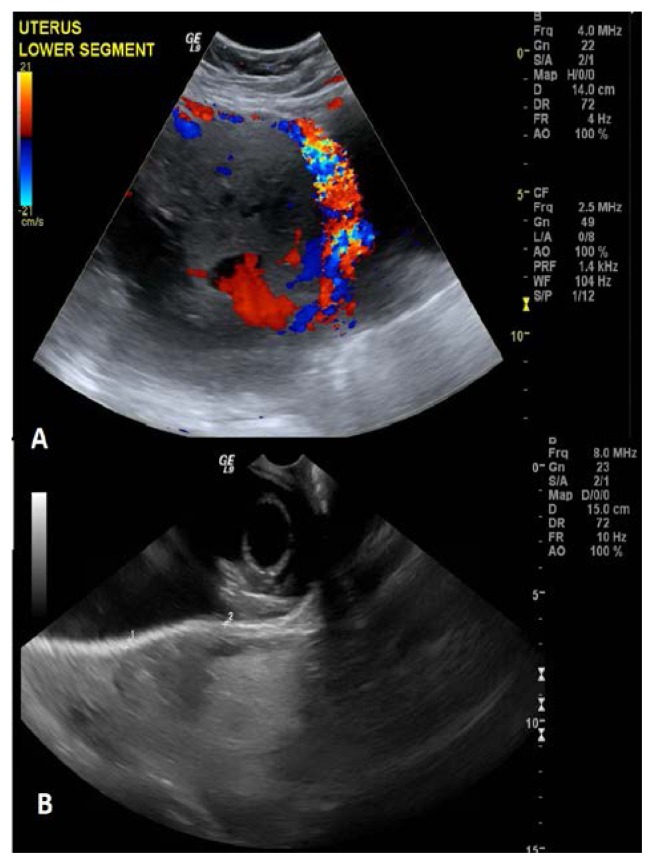

Introduction: Placenta percreta is an abnormality of placentation where it invades the serosa and can go beyond it. Complications include massive hemorrhage, bladder dysfunction, and severe infections during delivery. The aim of this study is to report a complex case of placenta percreta managed by interval hysterectomy.

Case presentation: Pre-operative: 34 years old patient with previous three cesarean sections was followed in antenatal clinic. She came with repeated bouts of vaginal bleeding at 30-31 weeks. At 32 weeks and 4 days classical cesarean section was done with placenta left in situ. Prophylactic bilateral internal iliac artery balloon was inserted. Post cesarean section, uterine artery embolization was performed. Post-operative: Clinical features of pulmonary embolism (PE) developed about 4 hours later. Post-Operative Day 13: Total abdominal hysterectomy was done. After few days of discharge, the patient presented to the emergency department with shortness of breath. She was consequently diagnosed with chronic pulmonary embolism and treated with warfarin.

Conclusion: This is a case of placenta percreta managed by interval hysterectomy. However, the most widely accepted method of management is cesarean hysterectomy. In this case, interval hysterectomy was done due to the possibility of bladder invasion by placenta, to decrease the amount of blood loss and to reduce the number of days stayed in hospital. Appropriate management for the patient must be personalized, whether it is by cesarean hysterectomy or interval hysterectomy, as each has risks and benefits.